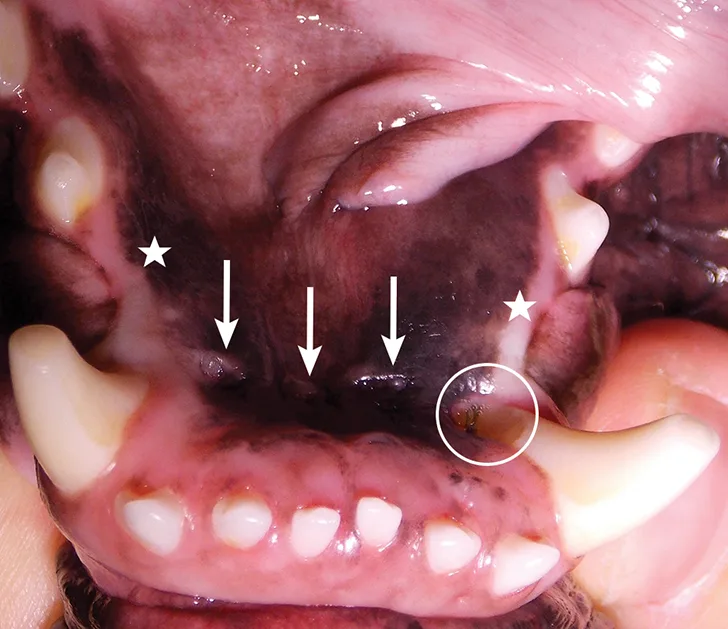

A thorough evaluation of the oral cavity (Figure 2) was performed with the patient under general anesthesia. Mandibular first premolars were not visible on clinical inspection. Mandibular mucosal trauma by the maxillary incisors and trauma to the left mandibular canine (304) tooth by the left second maxillary incisor (202) were observed. The patient also had oral masses present at the gingiva of the left rostral maxillary area covering the buccal surface of the premolar teeth (Figure 1).

FIGURE 2

Oral examination revealed nonvisible mandibular first premolars (stars), mandibular mucosal trauma by the maxillary incisors (arrows), and trauma to the left mandibular canine tooth (304) by the left second maxillary incisor (202; circle).